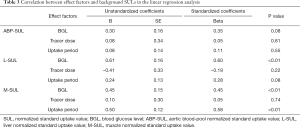

A linear regression analysis indicated there was a positive correlation between the variations of the L-SUL and the BGL (b=0.60, P<0.01). A similar result was found between the variations of the M-SUL and the BGL (b=0.45, P<0.01). The variation of the M-SUL also had a positive correlation with the variation of the tracer uptake period (b=0.58, P<0.01). There was no correlation between the variations of the ABP-SUL, the BGL, and tracer uptake period or between the variations of any background SULs and the tracer dose (all P>0.05). The effect of the BGL was more significant on the L-SUL than on the M-SUL (b=0.60 and 0.45, respectively). For the M-SUL, the effect of the BGL was less significant than that of the 18F-FDG uptake period (b=0.45 and 0.58, respectively; Table 3).